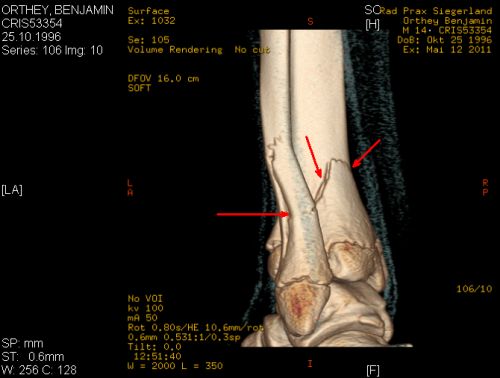

Der Junge auf dem Bild oben ist mein Sohn Benjamin, … genannt „Benni“. Benni ist 14 Jahre alt und ein begeisterter Inline-Skater. Er fährt wirklich gut, … ohne Risiko und sehr sicher (in letzter Zeit sogar mit Helm!).

Kurz darauf waren wir bereits vor Ort. Und das DAK Krankenhaus Hachenburg liegt glücklicherweise direkt um die Ecke. Nach der Aufnahme in der Unfall-Ambulanz stand relativ schnell fest: TRIPLANE-Fraktur, … ein komplizierter 3-Ebenen-Bruch am linken Sprunggelenk: … 1. Schienbein gebrochen, … 2. Wadenbein gebrochen, … 3. diverse Abplatzungen vom Knochen.